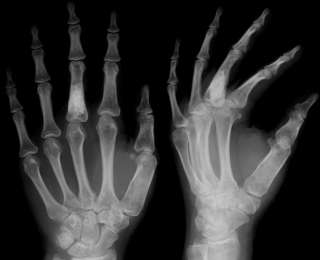

1. Обручальное кольцо Берты Рентген

В ноябре 1895-го года профессор физики Вильгельм Конрад Рентген из Вюрцбурга, Бавария, изучал «электрические лучи», когда обнаружил, что они могут проникать сквозь объекты и проецировать изображения этих объектов на флуоресцентный экран. Когда он поместил на пути лучей свою руку, то заметил, что изображение показало контраст между костью и полупрозрачной плотью. Рентген мгновенно понял последствия своего открытия: теперь врачи могли исследовать организм человека без вскрытия. Он заменил флуоресцентный экран на фотографическую пластину и 8 ноября 1895-го года сделал первый рентгеновский снимок. На снимке была левая рука его жены, Берты и её обручальное кольцо.